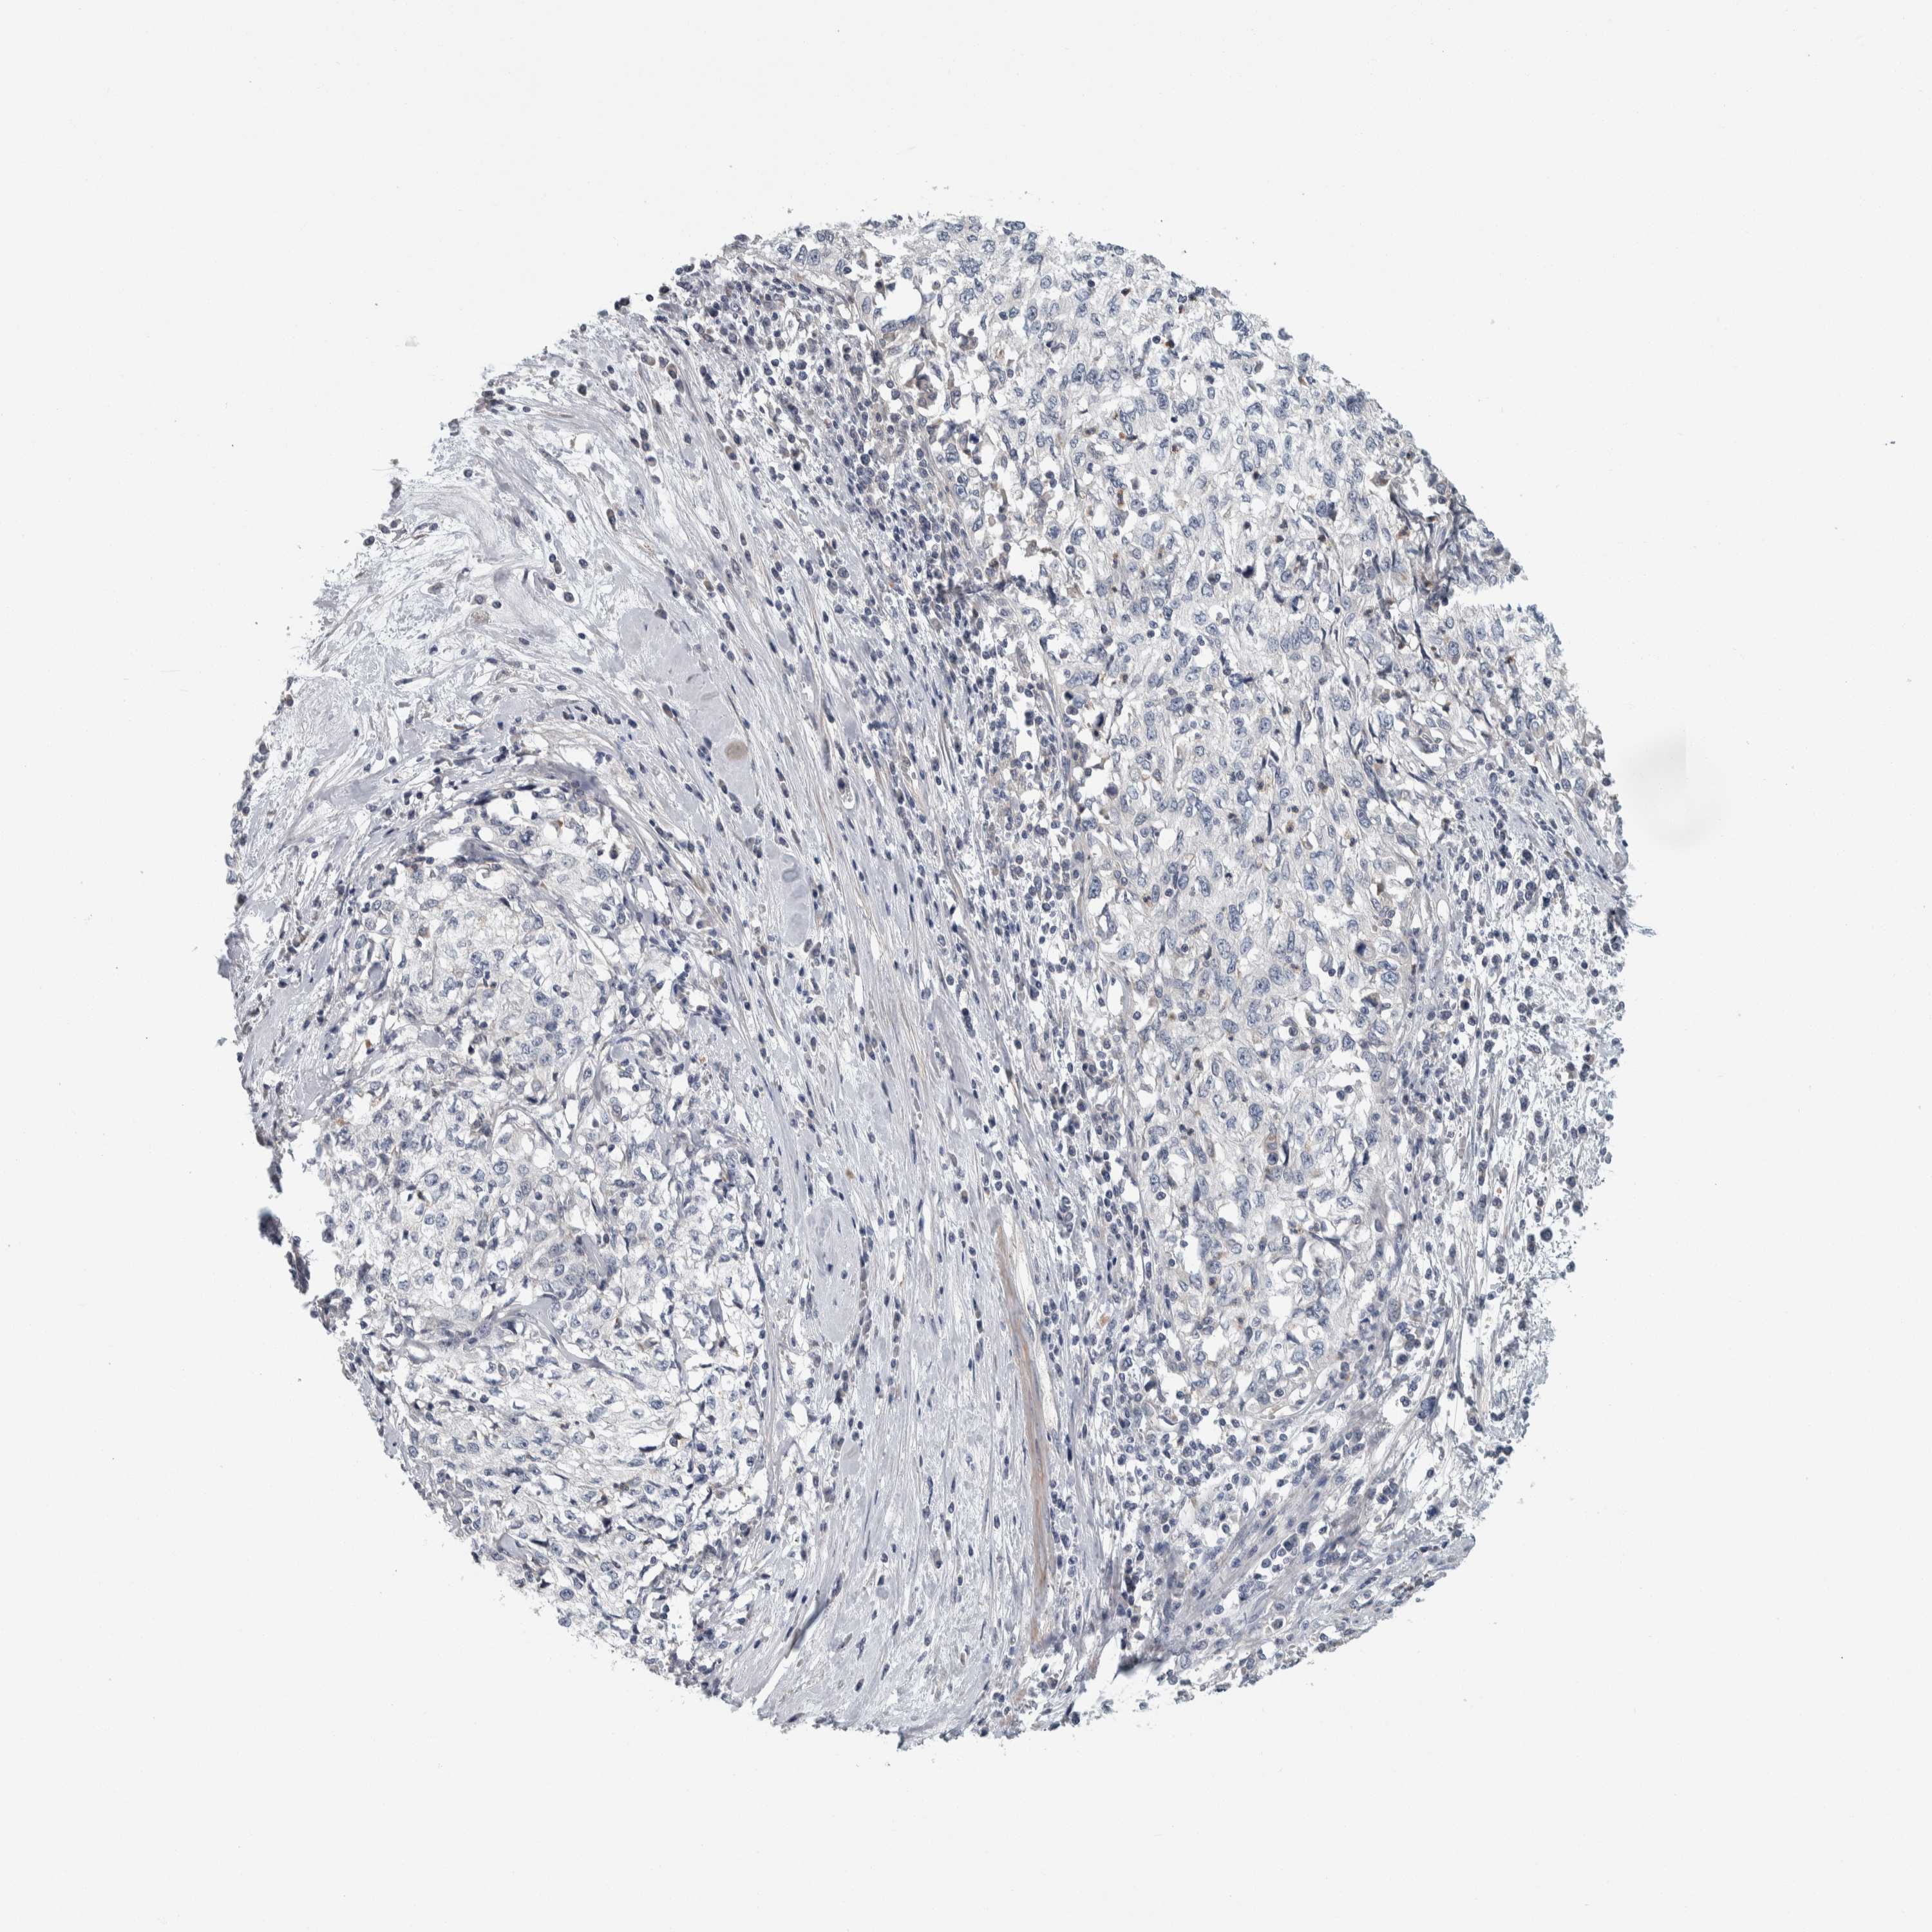

CERVICAL CANCER - Protein expressioni

A mouse-over function shows sample information and annotation data. Click on an image to view it in a full screen mode. Samples can be filtered based on level of antibody staining by selecting one or several of the following categories: high, medium, low and not detected. The assay and annotation is described here.

Note that samples used for immunohistochemistry by the Human Protein Atlas do not correspond to samples in the TCGA dataset.

Antibody stainingi

Antibody staining in the annotated cell types in the current human tissue is reported as not detected, low, medium, or high, based on conventional immunohistochemistry profiling in selected tissues. This score is based on the combination of the staining intensity and fraction of stained cells.

Each image is clickable and will lead to virtual microscopy that enables deeper exploration of all samples and also displays staining intensity scores, fraction scores and subcellular localization as well as patient and tissue information for each sample.

Antibody HPA024231

Staining

High

Medium

Low

Not detected

Intensity

Strong

Moderate

Weak

Negative

Quantity

>75%

75%-25%

<25%

None

Location

Nuclear

Cytoplasmic/membranous

Cytoplasmic/membranous,nuclear

Squamous cell carcinoma, NOS

Adenocarcinoma, NOS